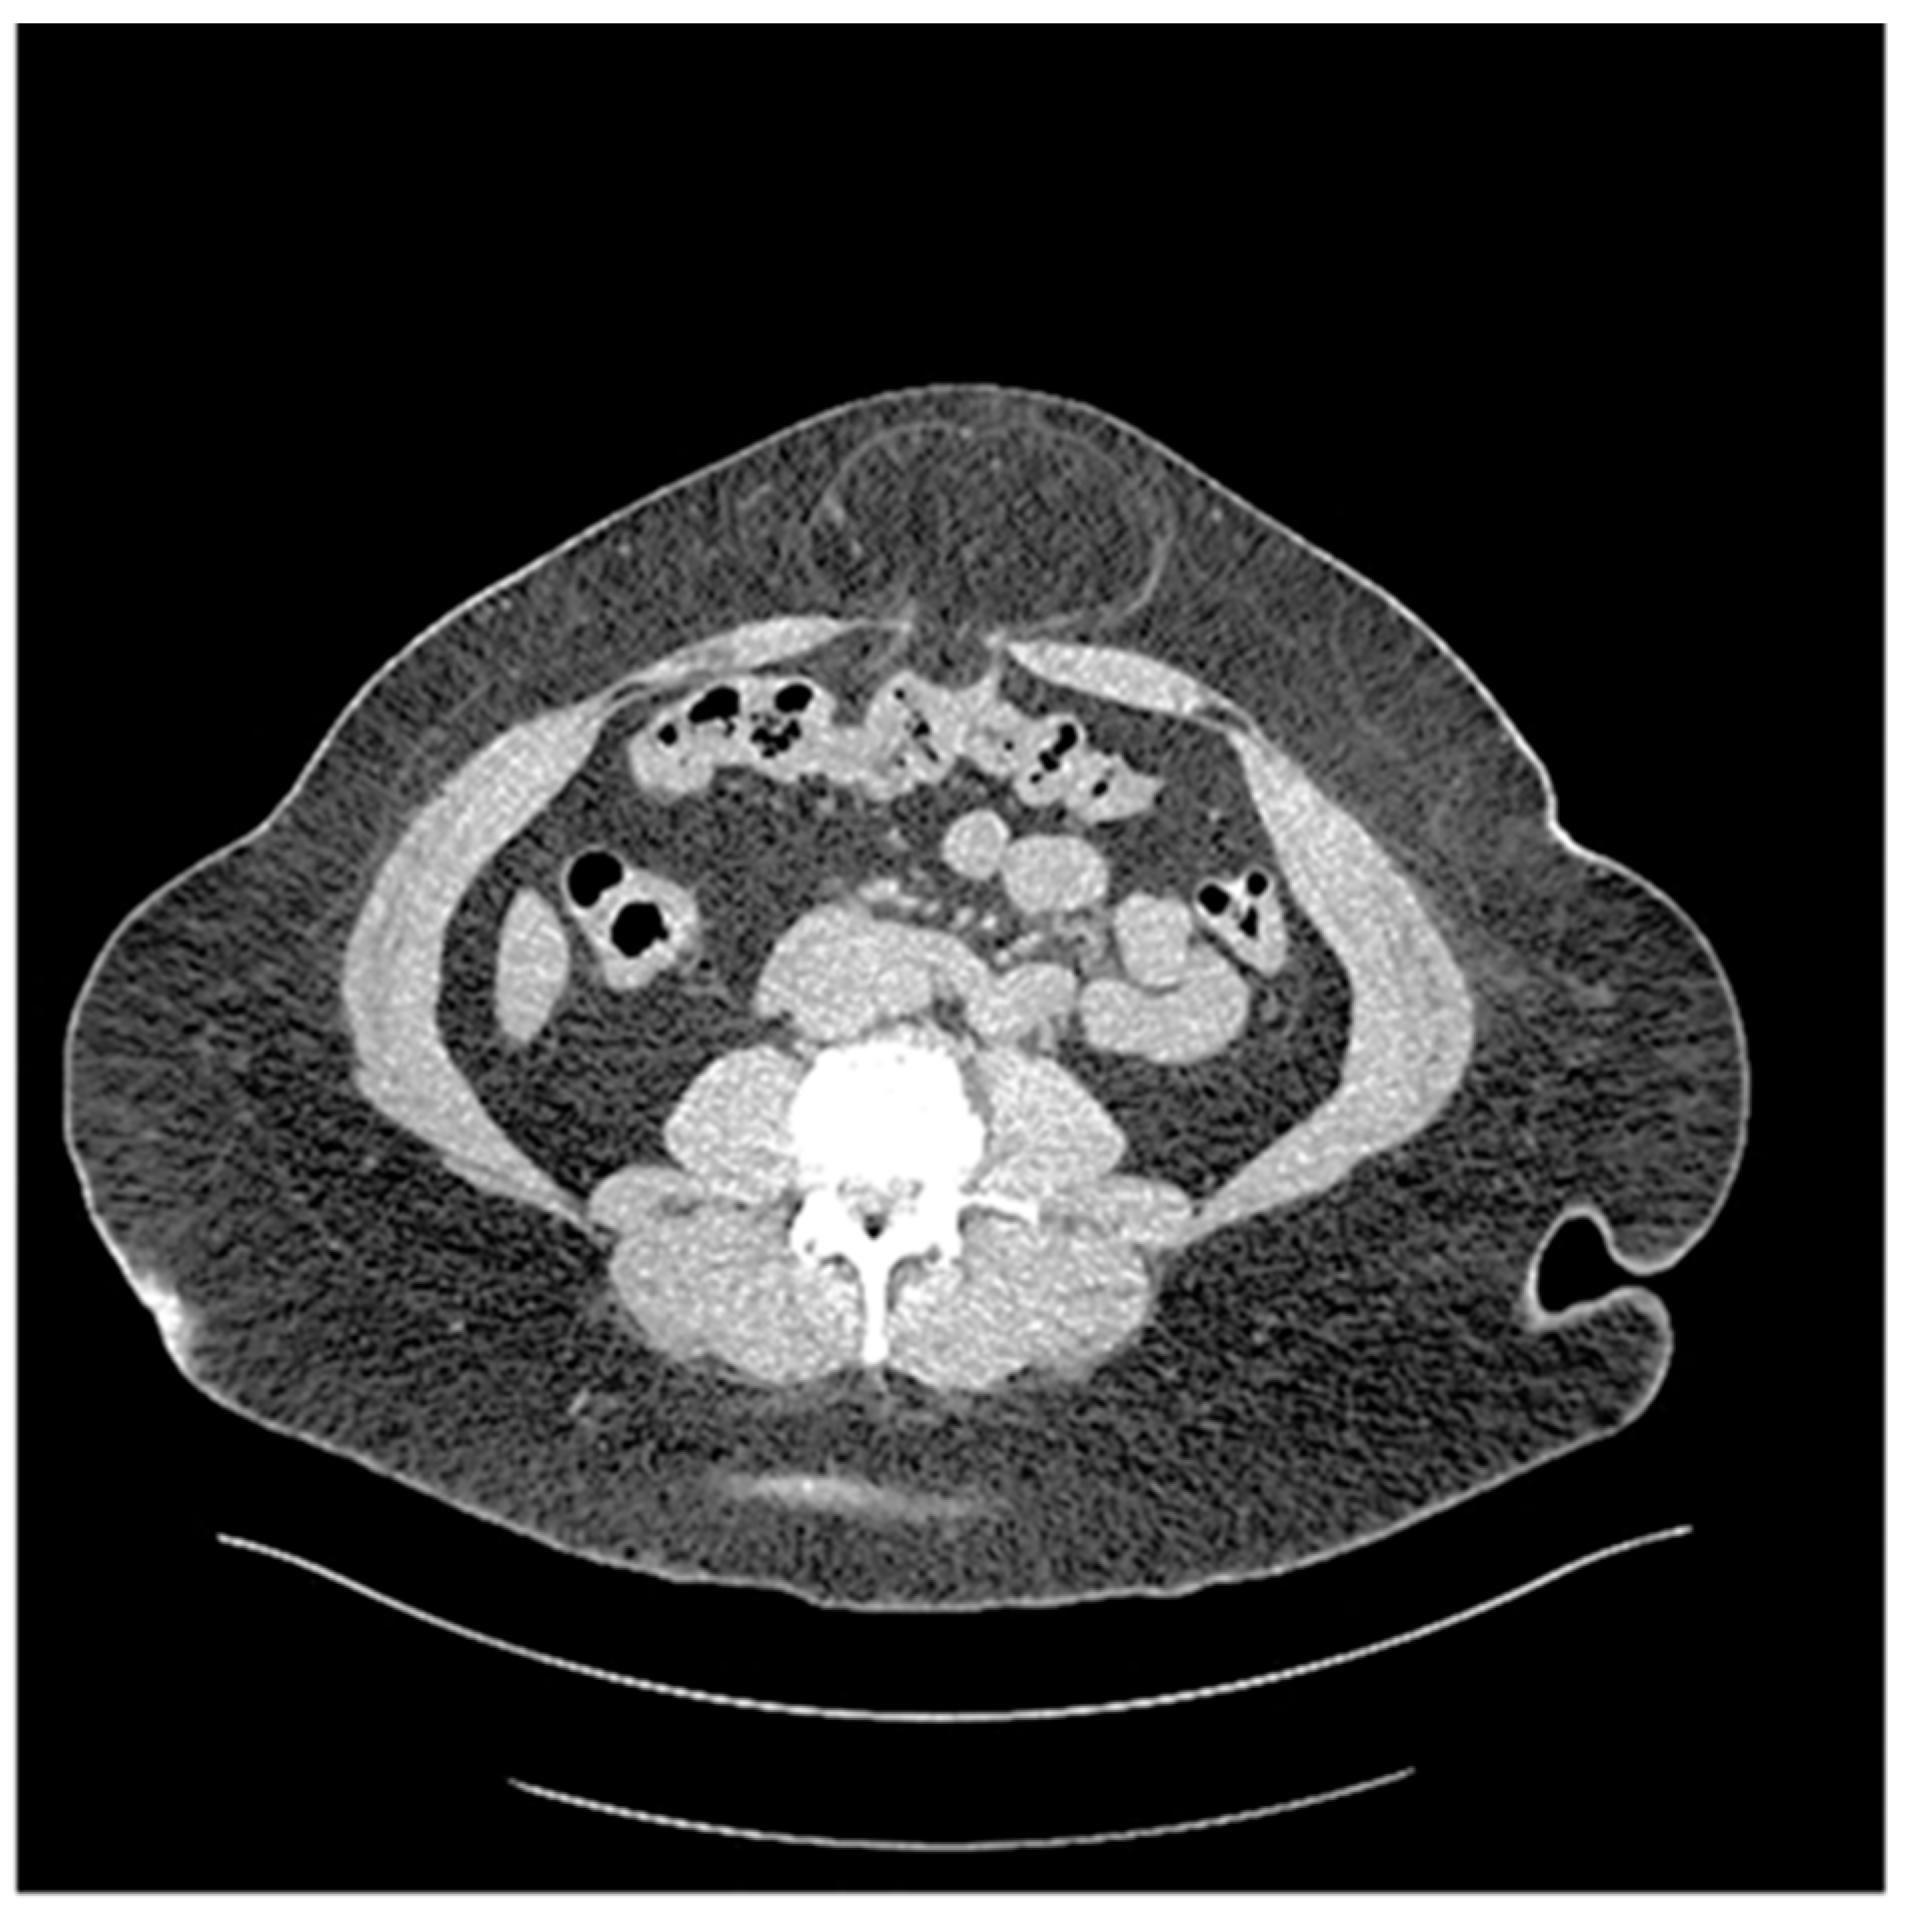

The rationale for placing mesh in obese patients (BMI ≥ 30 kg/m2) with UH is that these patients have relatively higher intraabdominal pressure compared to non-obese patients, thus increasing recurrence risk as well as incarceration (Figure 6).

Figure 6. Chronically incarcerated Umbilical hernia in a patient with a BMI 39.3 kg/m2.